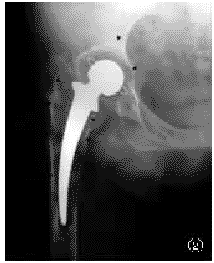

图2股骨柄假体周围膨胀性骨溶解(箭头所示)连接成片如蜂窝状

图3股骨近端Gruen一、七区膨胀性骨溶解,股骨柄假体下沉

膨胀性骨溶解倾向于在各区内单发,但亦有严重者在假体周围连接成片,如蜂窝状(图2~5)。